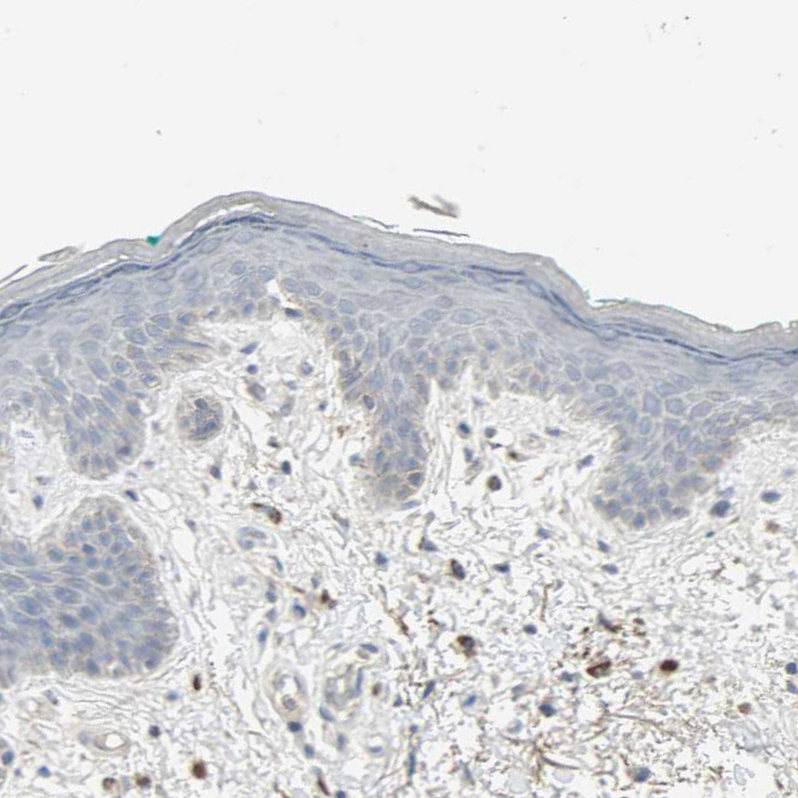

Immunohistochemical staining of human cerebral cortex shows strong nuclear positivity in neurons.